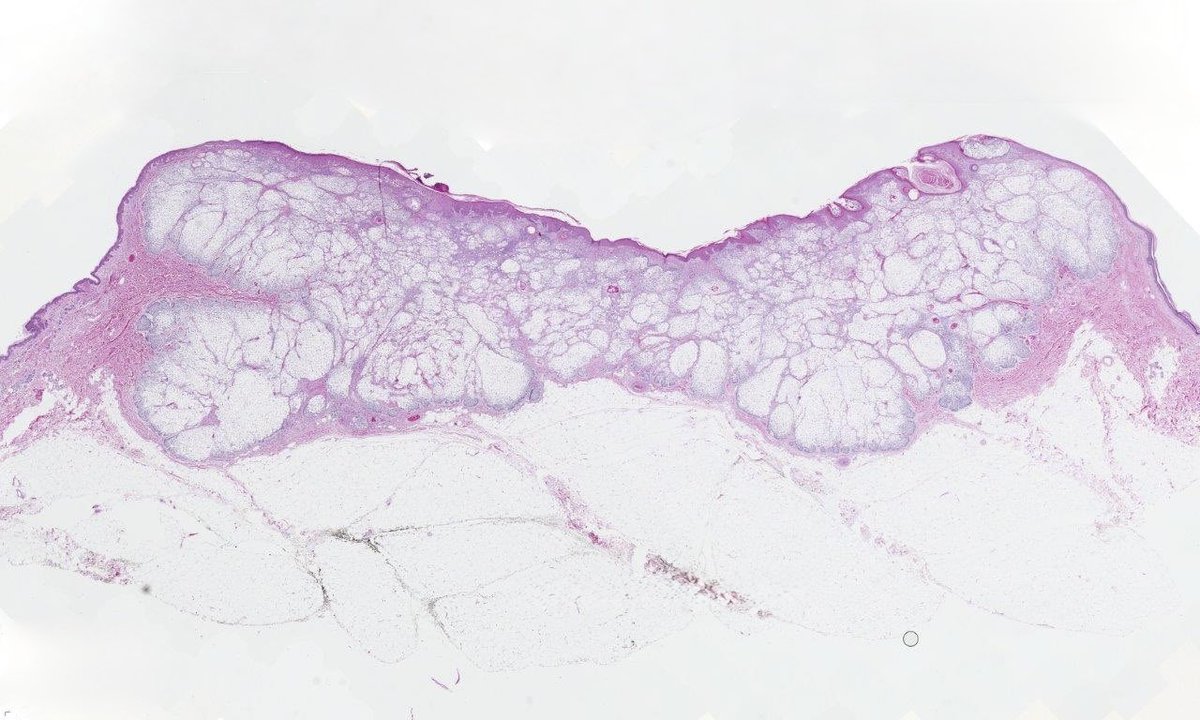

Clear cell BCC; a rare histologic variant caused by phagolysosomal vacuoles or excess glycogen accumulation. No prognostic implications; it behaves like ordinary BCC. Key is not mistaking it for clear cell SCC, sebaceous neoplasms, or metastatic RCC. #Pathtwitter #dermpath